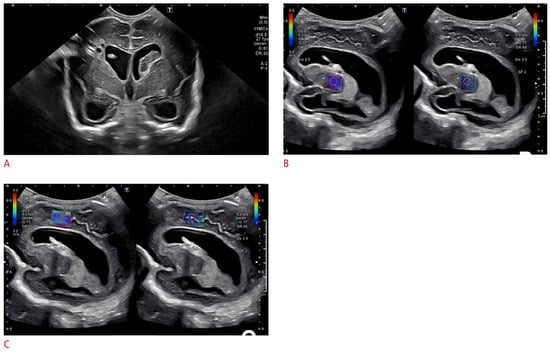

- Hwang, M.; Zhang, Z.; Katz, J.; Freeman, C.; Kilbaugh, T. Brain contrast-enhanced ultrasonography and elastography in infants. Ultrasonography 2022, 41, 633–649. [Google Scholar] [CrossRef]

- Freeman, C.W.; Hwang, M. Advanced ultrasound techniques for neuroimaging in pediatric critical care: A review. Children 2022, 9, 170. [Google Scholar] [CrossRef] [PubMed]